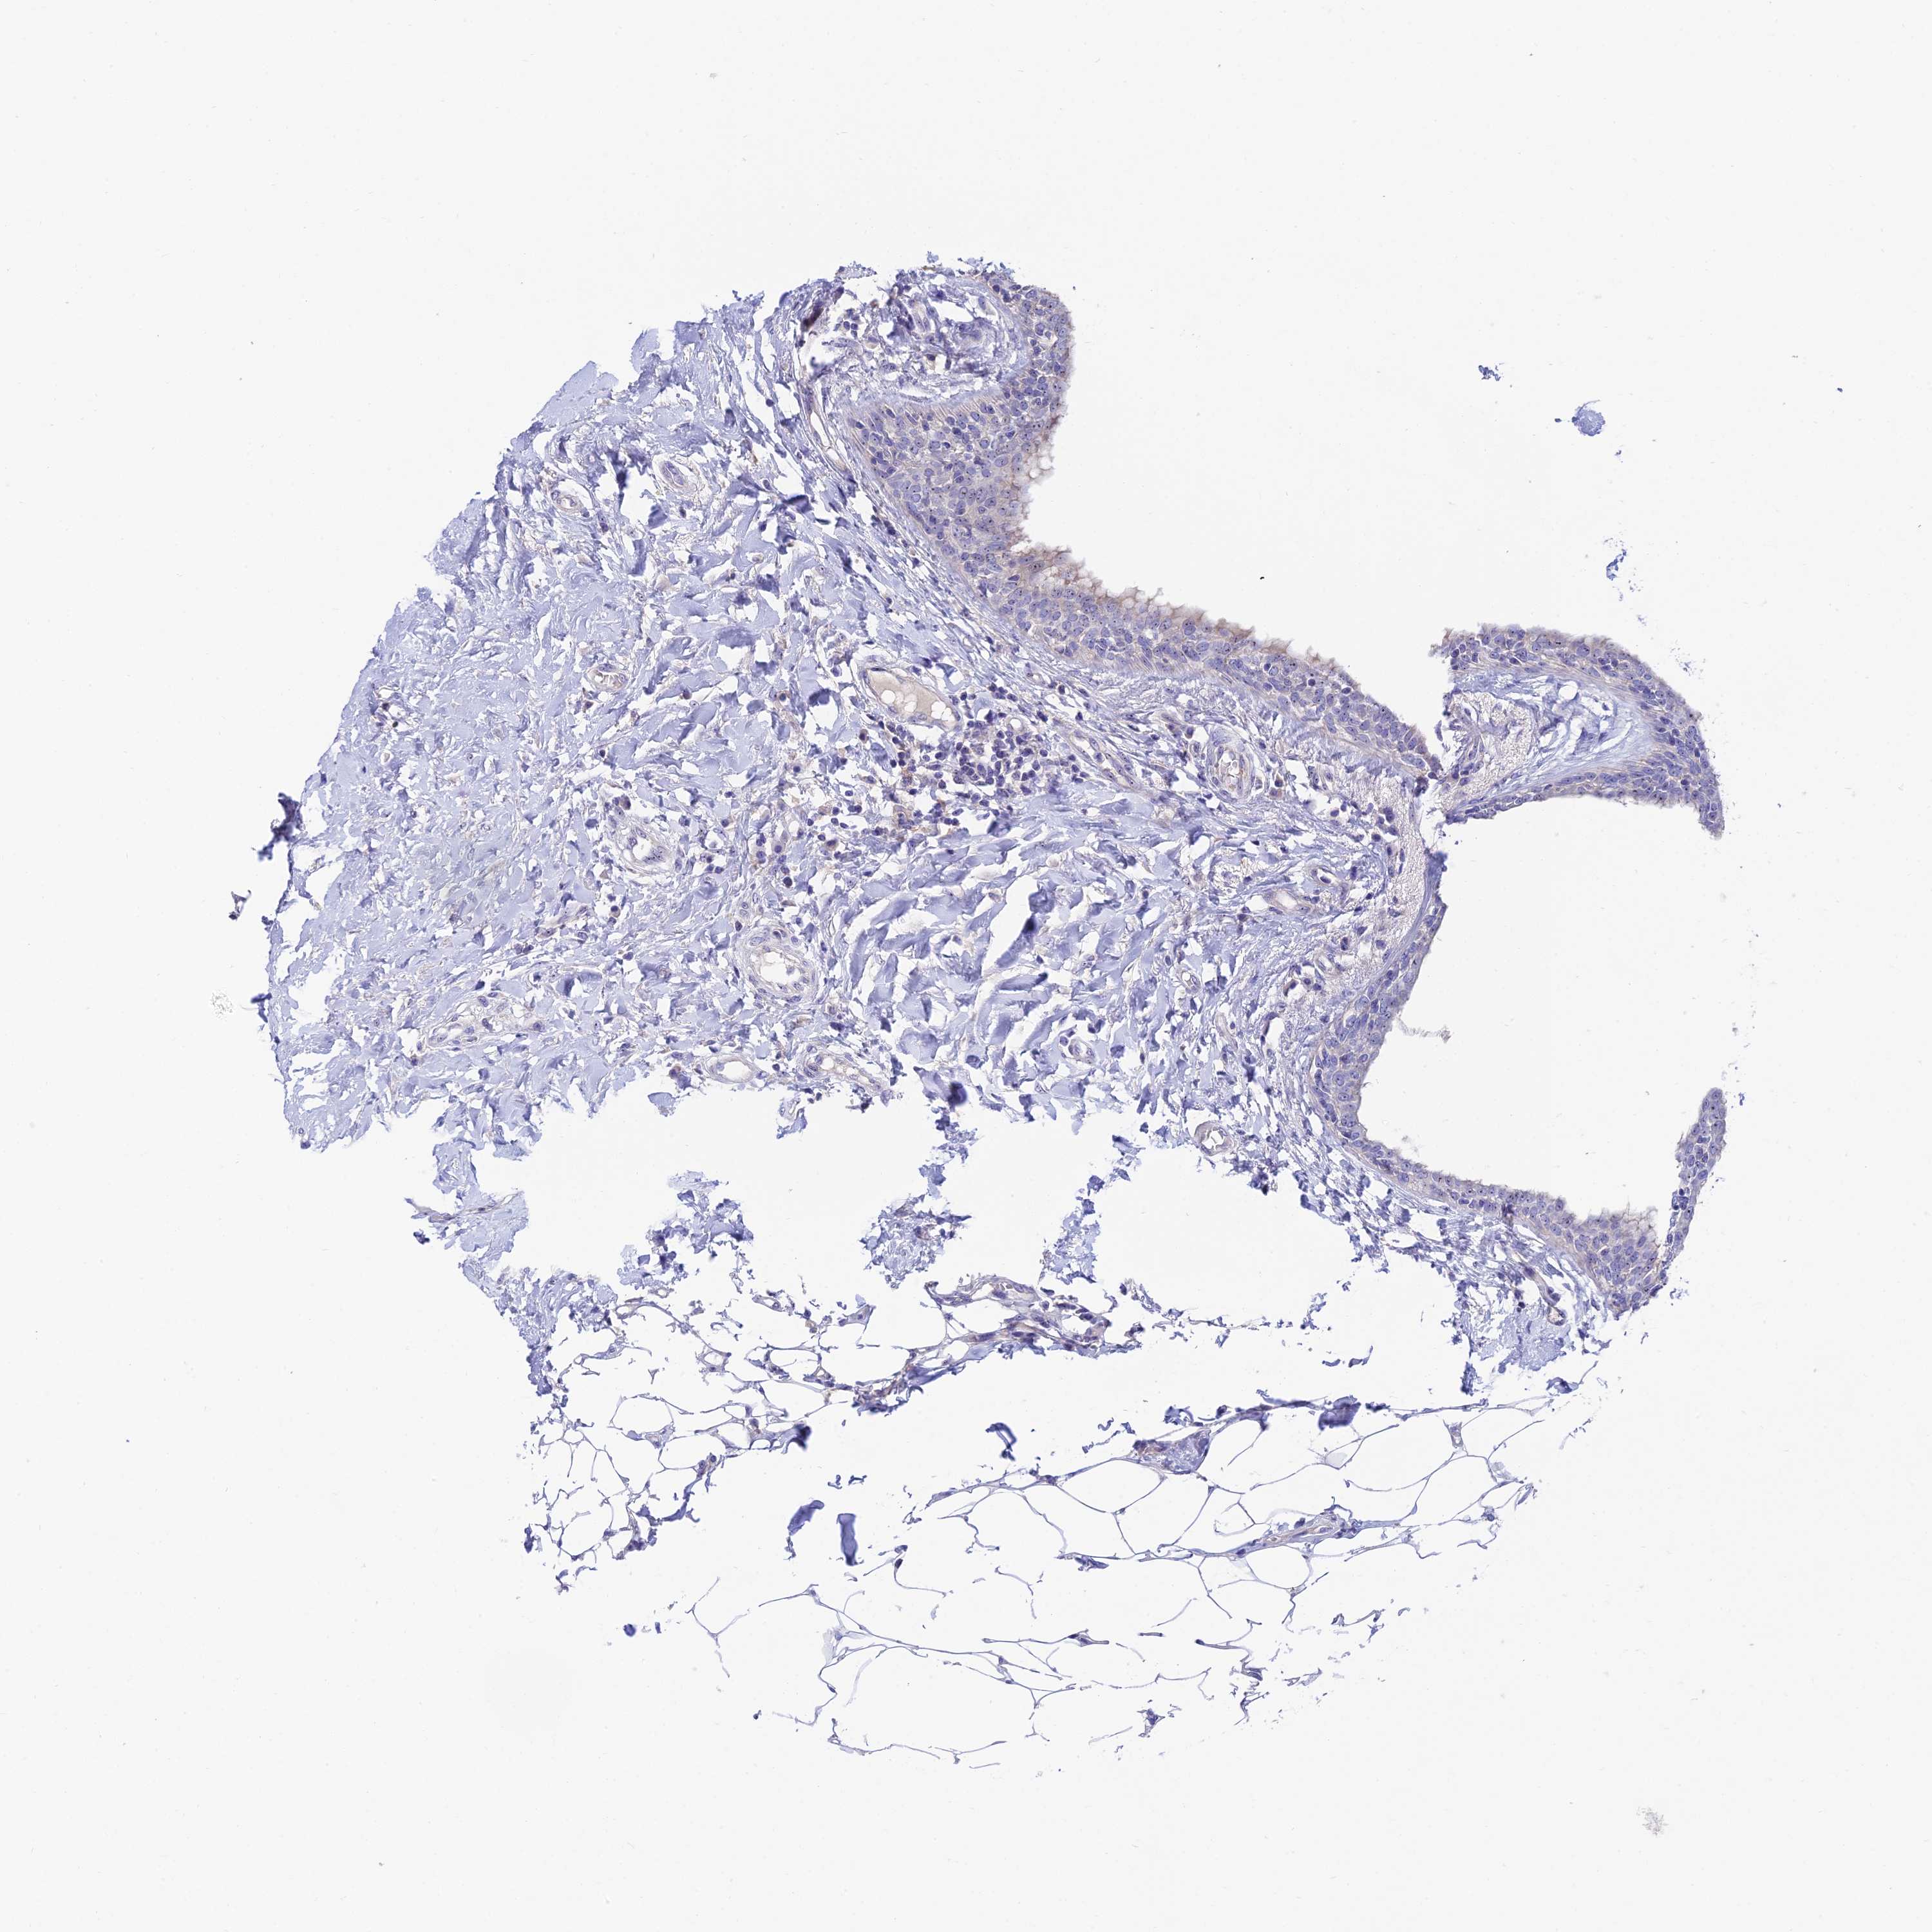

CANCER BREAST CANCER Show tissue menu

Breast cancer

Human cancer